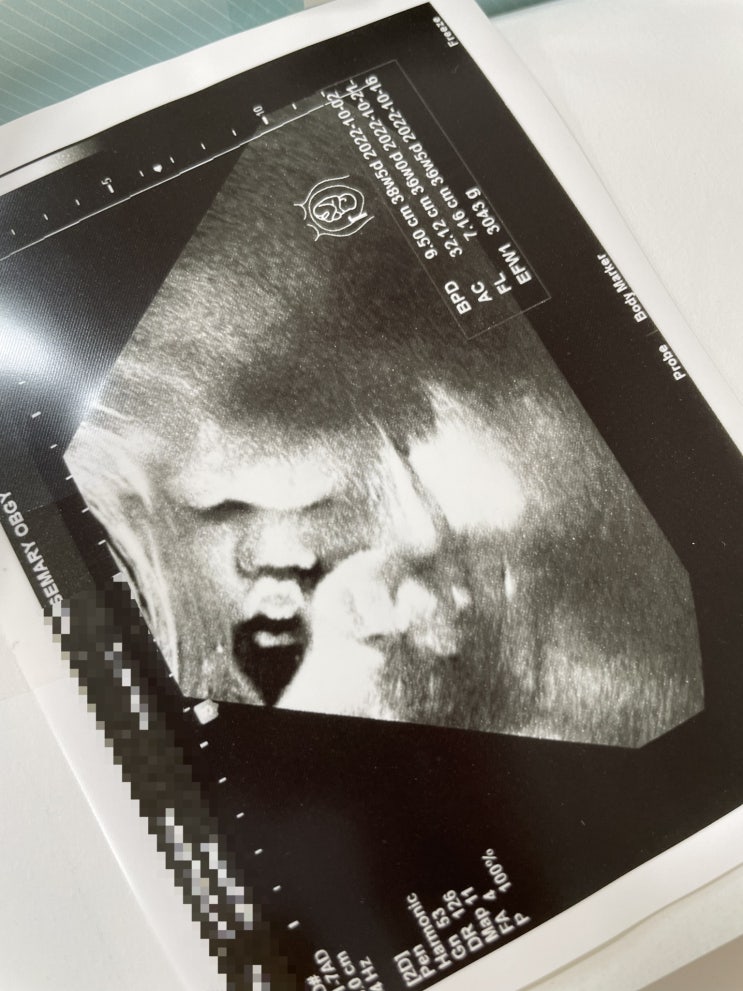

[임신39주] 똘똘이 태어나다

#임신일기 39주 [2022.10.10] 64kg 111/62 똘똘이 3475g 마지막진료끝으로 이제는 똘똘이가 세상밖으로 나...